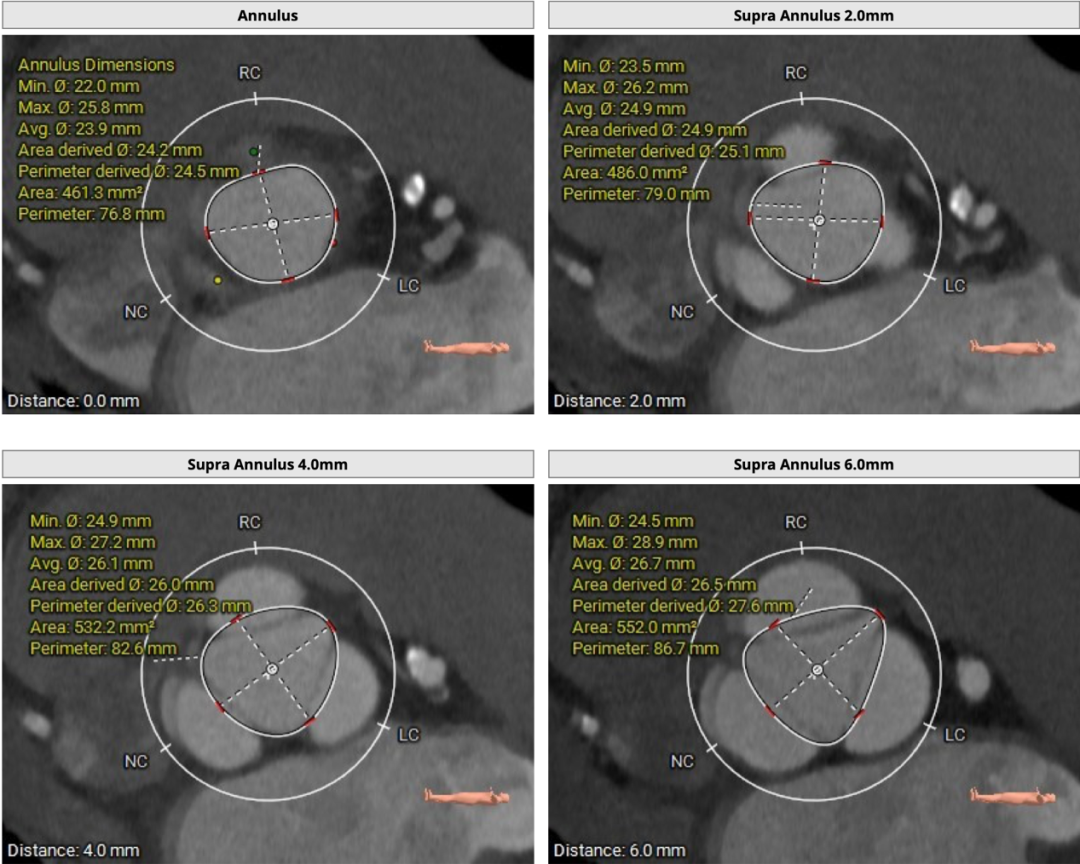

CT分析

主动脉瓣三叶式,瓣叶基本等大,瓣叶稍增厚,瓣叶未见明显钙化。患者主动脉瓣环周长折算直径约26.8mm: